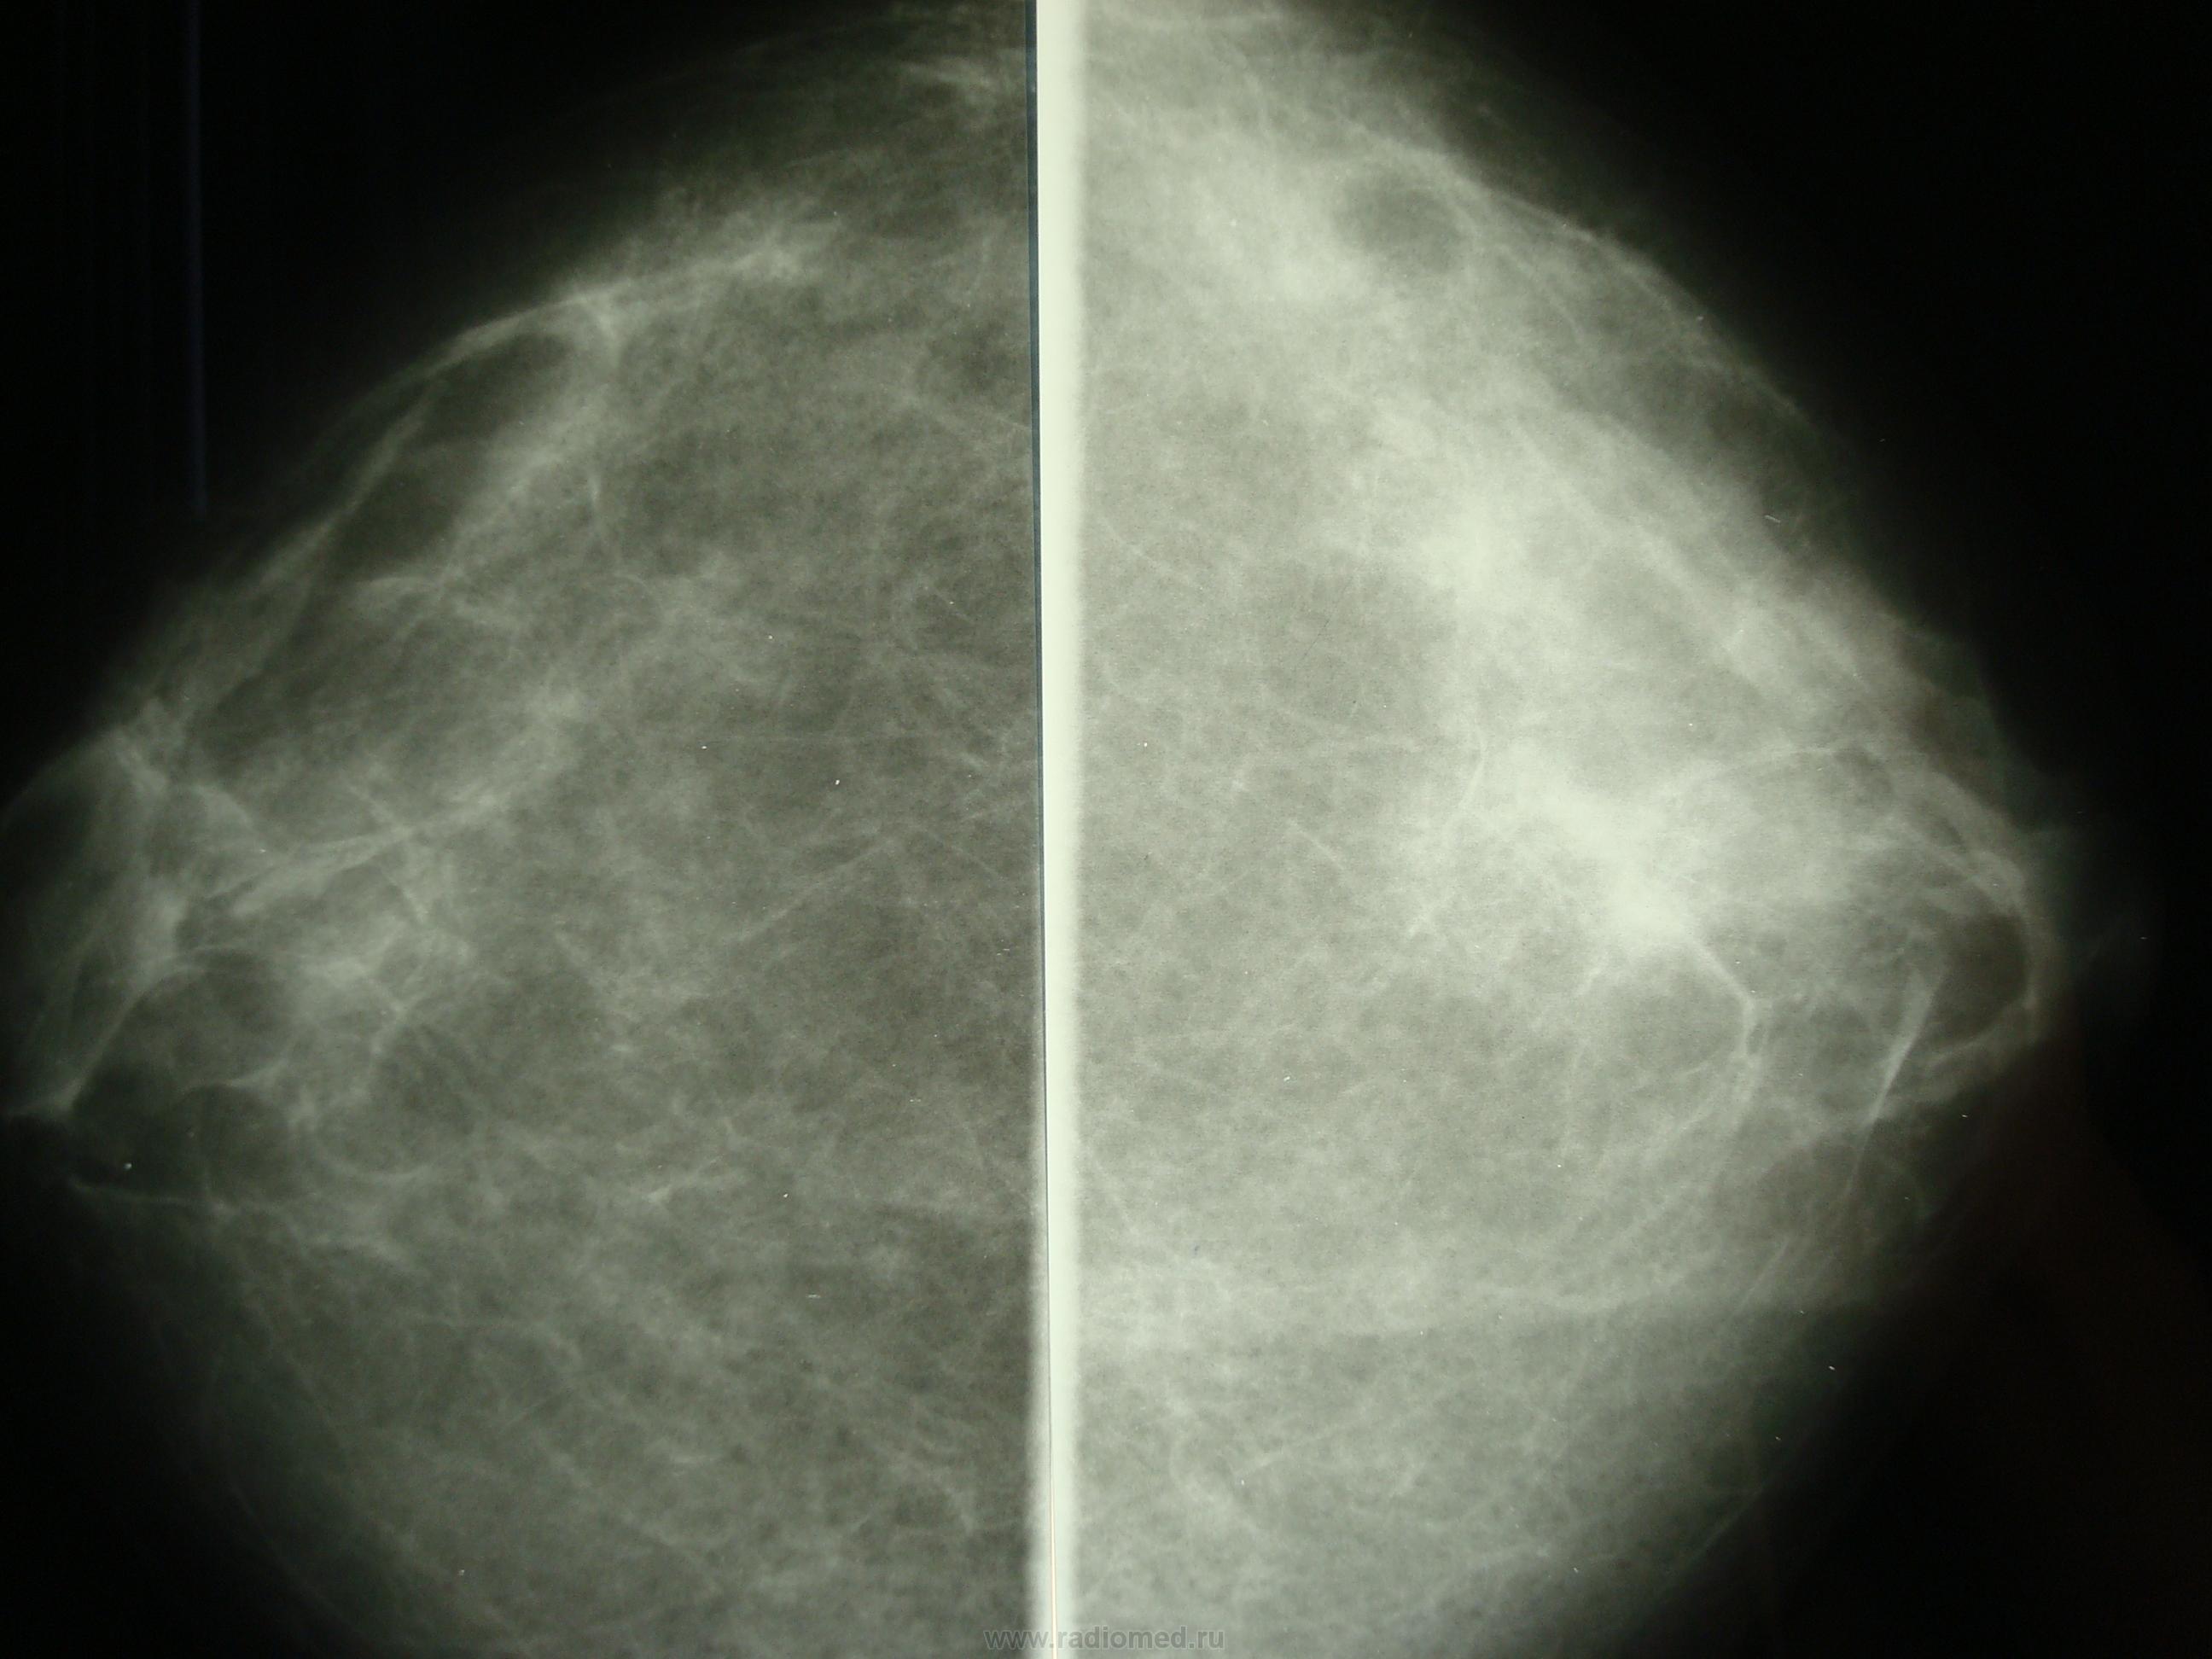

Что такое маммография: важность, процесс и результаты

Раздел: Необычные решения